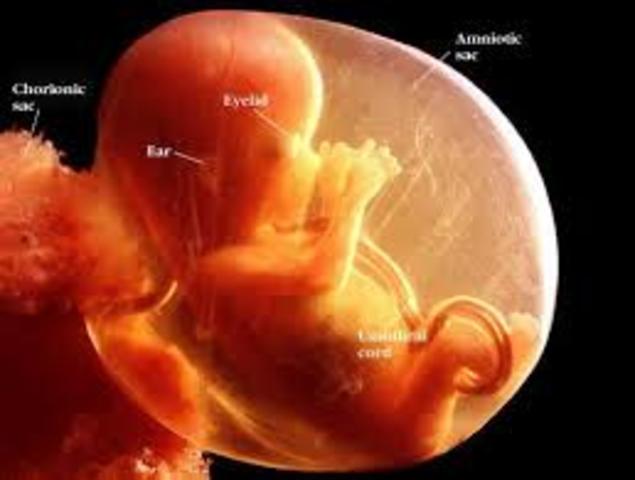

El ser que poco a poco va creciendo en tu interior ya deja de ser un embrión para convertirse en feto y se alimentará exclusivamente de la placenta a través del cordón umbilical. Por ello, es muy importante que comiences a tener una dieta sana y equilibrada porque será beneficioso para ti y el bebé.

El niño mide unos 6 centímetros y su peso oscila entre los 8 y los 14 gramos. La mayor parte de las estructuras internas ya están formadas y, a partir de ahora, seguirán perfeccionándose y creciendo. El aparato genital externo del bebé empieza a definirse, aunque con los ultrasonidos de la ecografíaaún no es posible distinguir el sexo del feto. Con esta semana, termina el período de "embriogénesis", durante el cual el embrión está más expuesto a los peligros que podrían perjudicar la correcta fo

¡Tu hij@ ya tiene el tamaño de un puño! Mide unos 9 centímetros, desde la cabeza hasta el coxis y pesa, aproximadamente, 25 gramos. Los órganos de los sentidos empiezan a perfeccionarse y los "detectores cutáneos" se definen. Ya siente el líquido amniótico que lo rodea y las paredes uterinas que lo envuelven.

Todas las estructuras básicas de su cuerpo ya están formadas. Ahora, sólo les queda crecer. Al final de esta semana, los brazos ya se verán proporcionados con el resto del cuerpo, aunque s

Hola Mamá, en esta semana tu bebé es casi un humano en miniatura, sus medidas alcanzarán los 21 cm de largo y llegará a pesar unos 550 gramos, sus pulmones están en desarrollo y segregan una sustancia llamada surfactante, que le ayudarán a introducir el aire en ellos cuando nazca. Recuerda que sus diminutos órganos se han ido formando, sus sentidos también están en pleno desarrollo, por lo que ya es capaz de sentir los estímulos que va recibiendo del exterior.